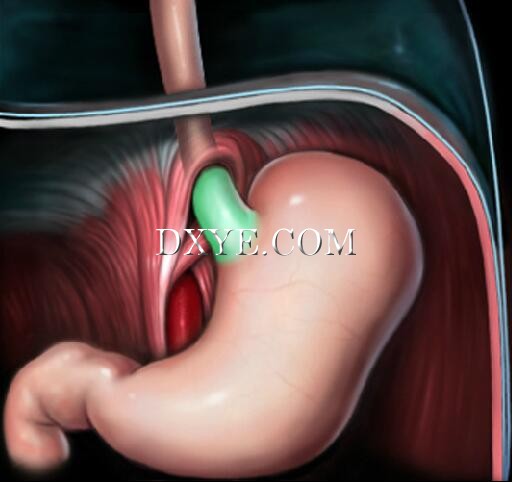

• Stage 3

Stage 3 sliding hiatal hernias have a shortened esophagus with fixation of the gastroesophageal junction above the diaphragm due to scarring.

True stage 3 hiatal hernias are rare.